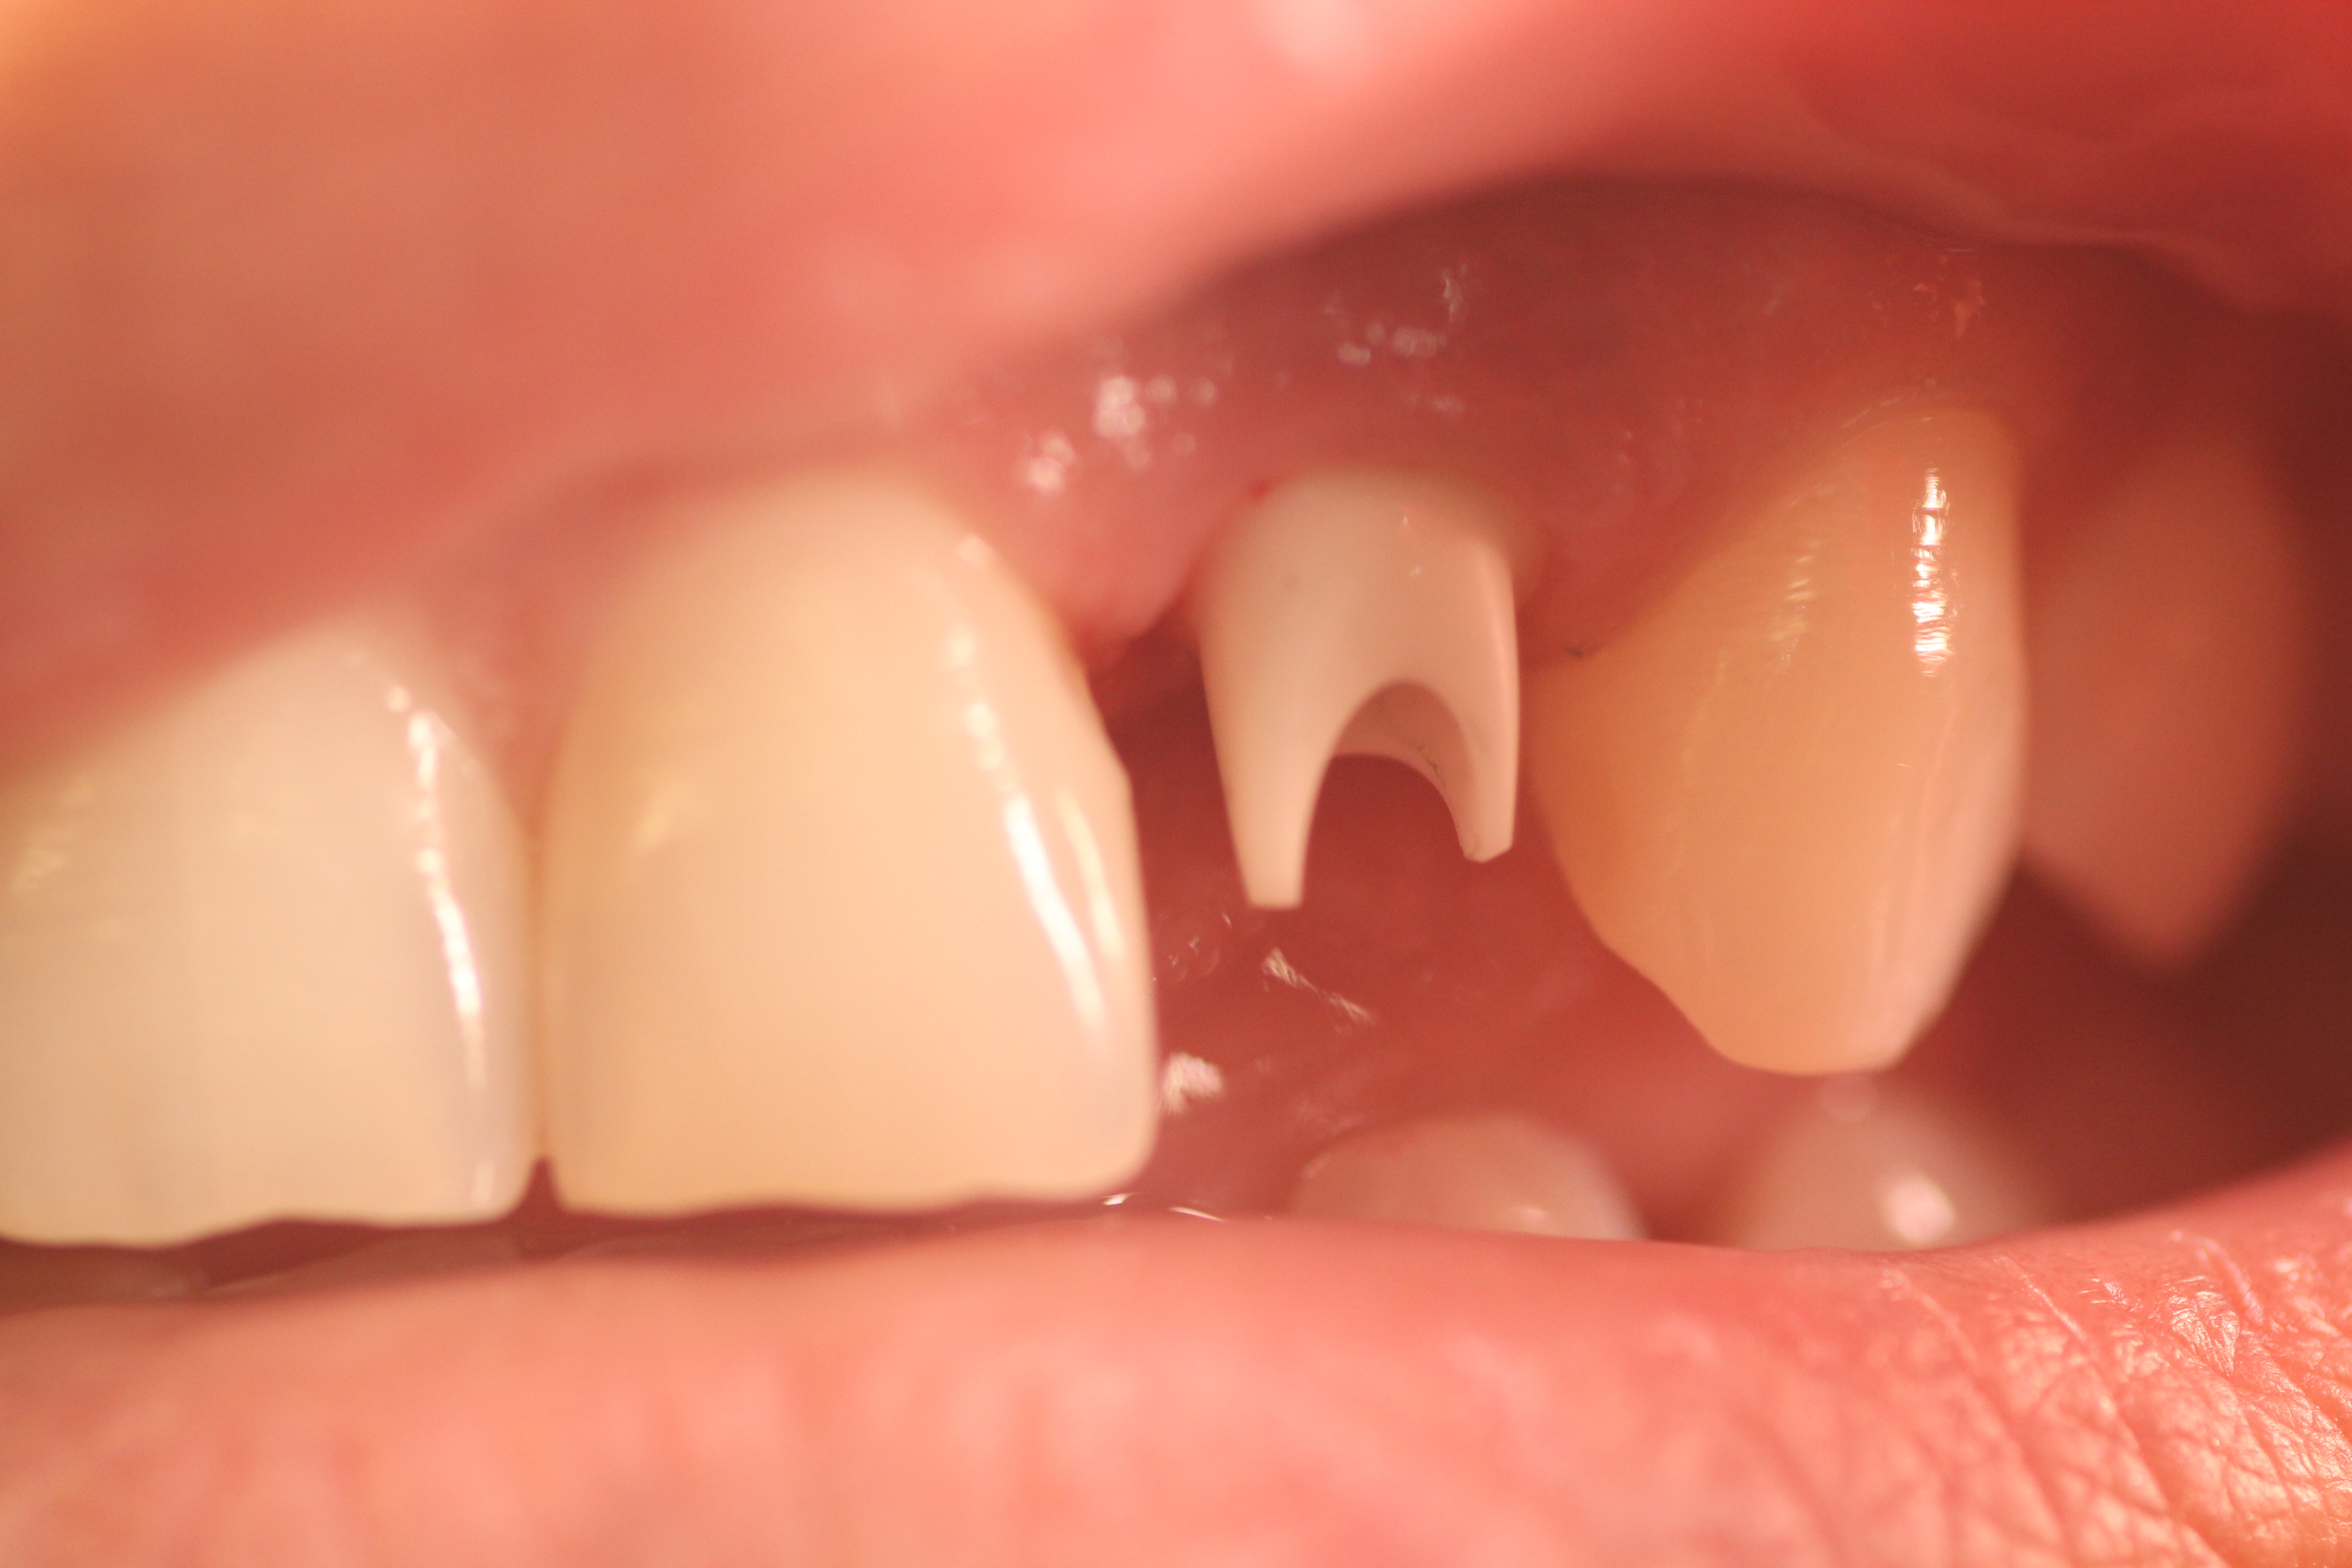

Case #1

Implant placement with immediate provisionalization in an aesthetic zone.

- Here is a patient that was not happy with her previous removable partial.

- Before Surgery.

- Temporary crown made.

- Temporary crown in place.